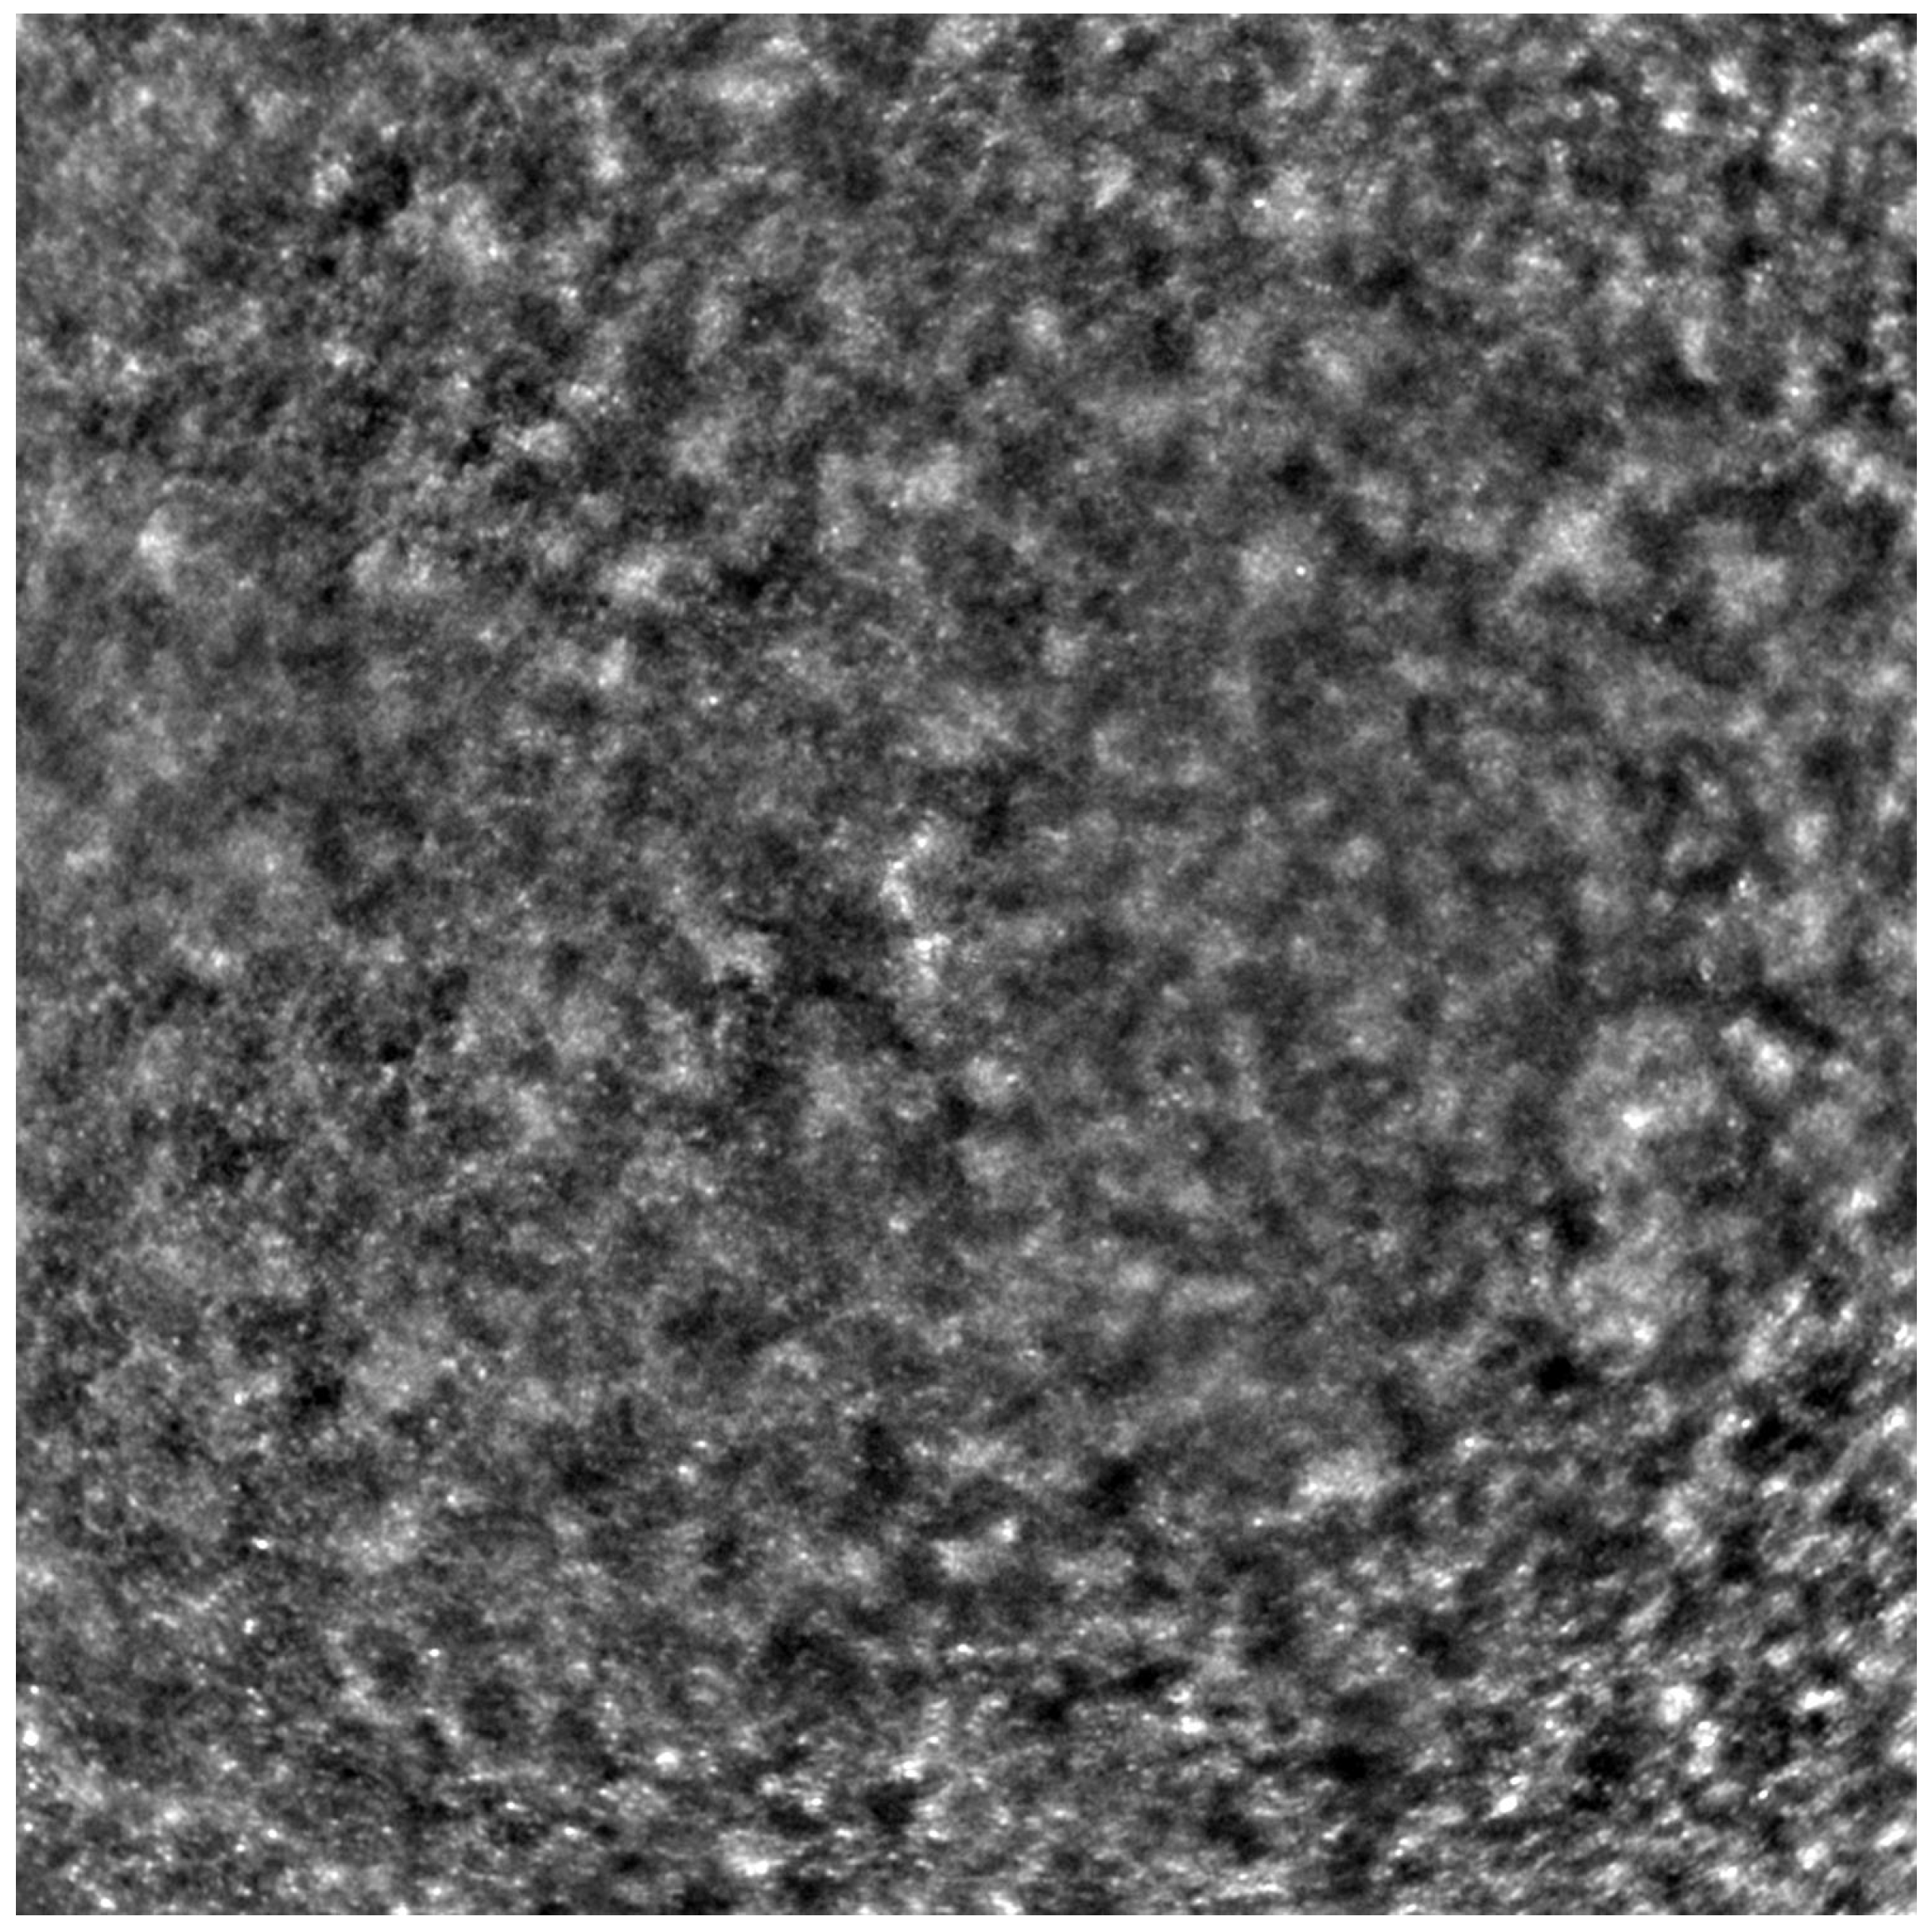

Adaptive optics retinal images depicting a healthy eye, CD, CRD, and STGD are presented in Figure 1, Figure 2, Figure 3 and Figure 4.

Figure 1 depicts the photoreceptor mosaic in a healthy eye. The image is taken paracentrally (2 ° superiorly) due to the limited ability of foveal image acquisition by Rtx™ [17]. By changing the focus point, the quality of an acquired image provides the assessment of photoreceptor parameters in parafoveal cones. The aberration and noise found in Figure 2, Figure 3 and Figure 4 are considered to be the result of poor fixation in eyes with impaired central vision in the course of macular disease. This issue has been addressed in our study. The assessment of factors predisposing for obtaining inadequate image quality was taken into consideration further in this article.

Cone mosaic disruption is an abnormality typical of IRDs. The cone and rod spacing is increased in IRDs compared to healthy retinas [18]. Additionally, poor image quality, likely resulting from inadequate fixation in eyes with low visual acuity, is a problem that, in some cases, makes image acquisition impossible [19,20]. In STGD, as well as in other IRDs, the “dark spaces” depicting areas of disrupted cone structure and abnormal cone reflectance have been described [21,22].

Figure 2. An adaptive optics image of the photoreceptors of an eye afflicted by cone dystrophy (Rtx1™, Imagine Eyes, France). Observe the cone disruption throughout the image with “dark spaces” apparent within the cone mosaic across different areas of the image.